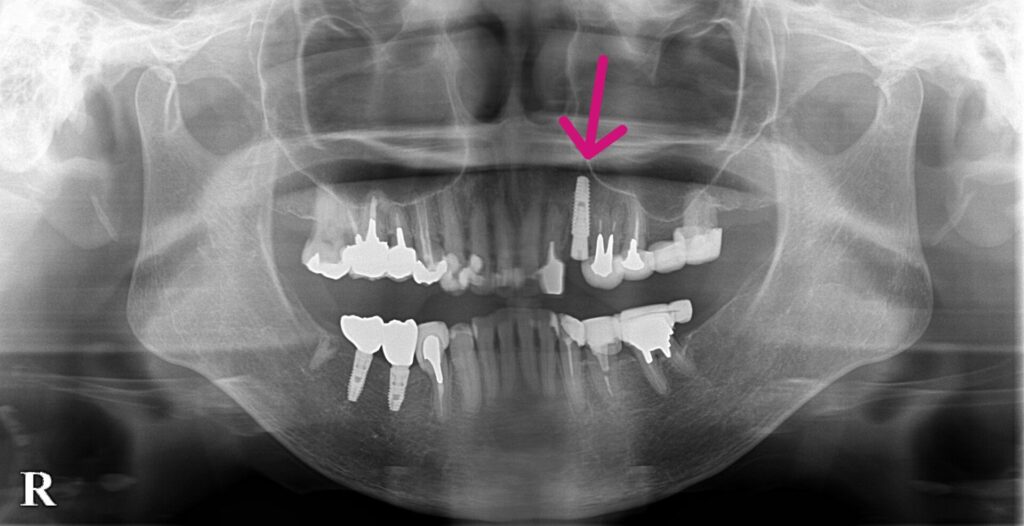

左上3歯根破折のため抜歯。

抜歯と同時にインプラント埋入。その日のうちに仮歯まで装着します。切開縫合を行わないため腫脹、痛みの少ない患者さんにやさしい術式になります。

左上3歯根破折。右下56は当院にてインプラント埋入

抜歯と同時にインプラント埋入。サージカルガイドを使用することにより正確な位置に埋入可能